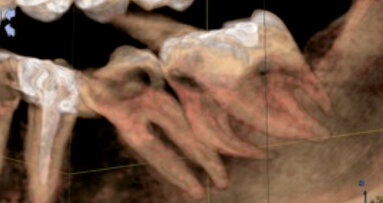

Per tutto il trattamento è stata utilizzata un’abbondante irrigazione (NaClO al 2,5%). I canali radicolari sono stati sagomati con una combinazione di frese Gates-Glidden e strumenti rotanti al NiTi. Ad alto ingrandimento, nella radice distale è stato trovato un ulteriore spazio canalare (Fig. 4). I residui della precedente otturazione canalare sono stati rimossi mediante una combinazione di strumenti manuali e rotanti e si è ottenuta una pervietà con piccoli strumenti manuali in acciaio. La lunghezza di lavoro è stata misurata con un localizzatore d’apice (Root ZX mini, J. Morita) e per la pre-sagomatura sono stati utilizzati strumenti rotanti PathFile (Dentsply Maillefer).

Si è prestata attenzione a non spingere accidentalmente il sigillante nel sito della perforazione. Il canale mesiolinguale è stato retro-otturato a un livello apicale della perforazione (Fig. 6). Dopo l’otturazione, è stato utilizzato MTA bianco, applicato con il dispenser MTA (entrambi Dentsply Maillefer), per sigillare il sito di perforazione. Come richiesto dal dentista del paziente, nel canale distale non è stato lasciato lo spazio per il perno in quanto voleva essere lui a creare lo spazio per posizionare un perno intra-radicolare (Fig. 7). Come materiale di otturazione provvisoria è stato utilizzato il Cavit G. Il paziente è stato rinviato al proprio dentista per il restauro finale e gli è stato fissato un controllo dopo sei mesi.

Le innovazioni nella tecnologia e nei biomateriali non hanno dimostrato di migliorare le percentuali di successo globale in endodonzia. Le perforazioni radicolari possono influenzare negativamente la prognosi. Nonostante ciò, il MO permette al clinico di lavorare con molta precisione anche nelle situazioni più impegnative, e l’uso di MTA migliora notevolmente il successo del trattamento di perforazioni nell’area della forcazione. Inoltre, l’uso degli ultrasuoni sotto ingrandimento ha facilitato la rimozione del perno, nonostante le sue dimensioni ridotte. L’irrigazione passiva con ultrasuoni ha rimosso in modo efficace i detriti e il tessuto necrotico dall’area dell’istmo mesiale, permettendo il riempimento con materiale d’otturazione, come osservato nella radiografia finale (Fig. 8).